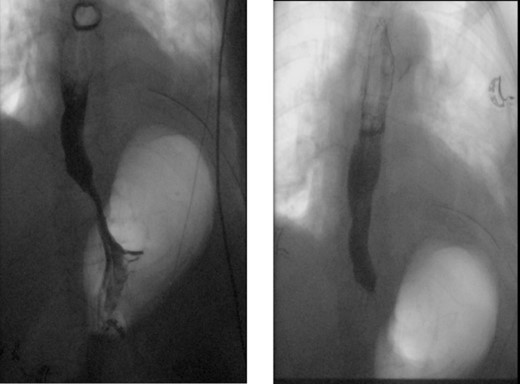

A 72-year-old woman with a past medical history of coronary artery disease and chronic gastroesophageal reflux disease (GERD) with hiatal hernia status postsurgical correction by Nissen’s fundoplication 20 years ago, presented with worsening episodes of intermittent dysphagia, heartburn, and postprandial cough of ~2 years duration but worsening symptoms over the past 2 months. She denies any symptoms of food regurgitation, nausea, vomiting, appetite, or weight changes. Upon her initial clinic evaluation, she had normal vital signs and unremarkable findings on the physical exam. The decision was made to start her empirically on a proton pump inhibitor, assuming her symptoms are related to GERD, to which she did not respond appropriately. A subsequent upper endoscopy revealed a large epiphrenic wide-mouthed ED (Fig. 1). Additionally, an esophagram showed a 6.0 × 5.0 cm epiphrenic ED with a 3.3 cm neck (Fig. 2). High-resolution esophageal manometry (HREM) was performed; thereafter, revealing a normal motility pattern (Fig. 3). She was then referred to cardiothoracic surgery for consideration of surgical repair. She was initially advised to follow a dysphagia-specific diet and wait conservatively on her symptoms, but no changes were observed in her clinical course over 6 months. The patient subsequently underwent a successful uncomplicated esophageal diverticulectomy with myotomy, conducted through a lateral thoracotomy. During surgery, an esophagogastroduodenoscopy (EGD) revealed an ED at 35 cm in the gastroesophageal (GE) junction at 40 cm in the epiphrenic region. A standard posterior lateral thoracotomy was performed in the serratus-sparing fashion, and the pleural space was entered at the seventh intercostal space. The esophagus was encircled with a Penrose drain lifting it up, and it was freed from the periaortic tissue, and the ED cleared off all muscle fibers. The diverticulum was excised from the esophagus using a purple load stapler with an EGD scope in place to prevent esophageal narrowing. A myotomy was performed from the GE junction proximally, with negative leak testing. The muscle layer was then imbricated over the area of diverticulectomy, and a chest tube was inserted for drainage. A postoperative esophagram confirmed no presence of an ED (Fig. 4). Immediately after the surgery, the patient had a complete resolution of her symptoms, and during her 1-year follow-up visit, she remained asymptomatic.

Normal X-ray esophagram fluoroscopy postdiverticulectomy with myotomy surgery.